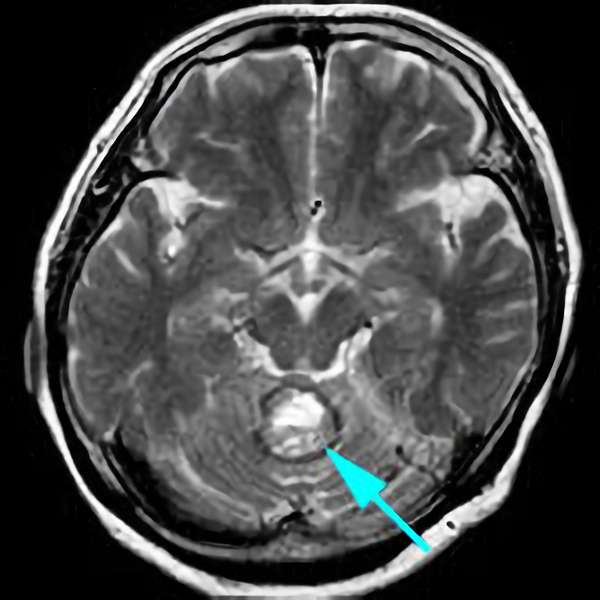

'25年10月

40代

南田,野本,元永

脳幹部

海綿状血管腫

出血の予防目的

熊本県の病院

No.No.62 手術前1

No.No.62 手術前2

No.No.62 手術後1

No.No.62 手術後2

No.No.62 摘出前

No.No.62 摘出中1

No.No.62 摘出中2

No.No.62 摘出後

CT/MRにより完全に摘出されたことが確認された